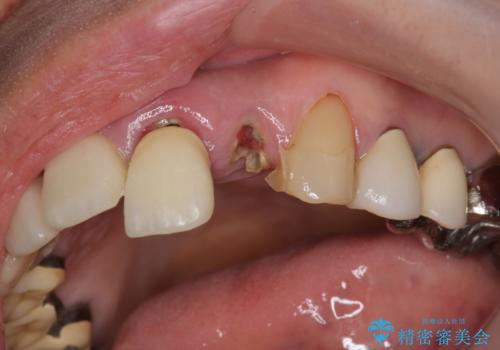

- 歩行中に躓いて転倒し、前歯2本がグラグラになってしまい痛み・審美性の改善を求めて来院されました。

X線検査・視診より強くぶつけた前歯は折れてしまい、抜歯が必要な状況です。

抜歯後の見た目改善として深い咬合関係であることからインプラントは避け、ブリッジで補綴治療を行っていくこととしました。

元々の噛み合わせが深く(ディープバイト)、転んで顎を強打したことで上顎前歯2本が根元から折れてしまい抜歯をしなければいけない状況となってしまいました。